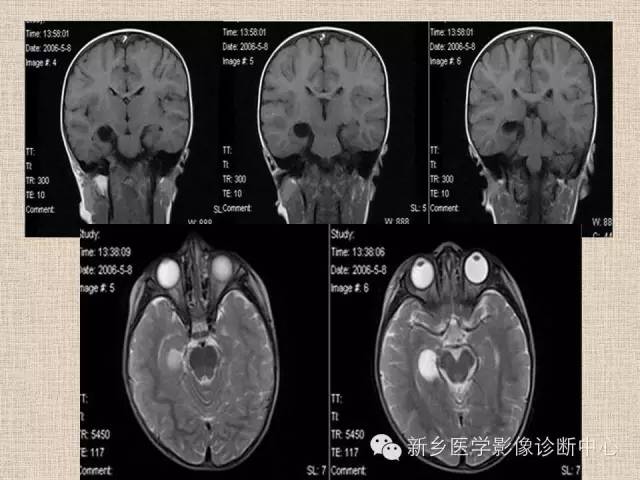

脉络膜裂囊肿一例